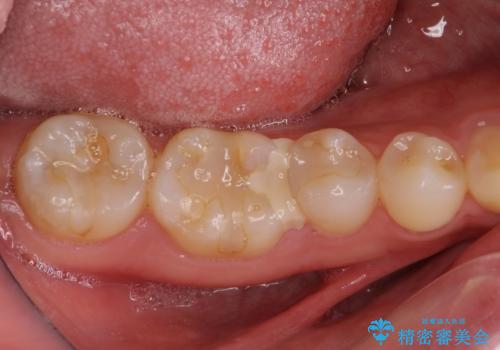

- 近医にて虫歯治療中に転院を希望とのことで来院された患者様です。

左上奥と右下奥に治療中の歯があり、虫歯を取っている途中で仮詰めの材料が充填されている状態でした。

仮詰め材を外すと虫歯が残っていたので、全てを取り除いた後に、ゴールドインレーの型どりを行いました。